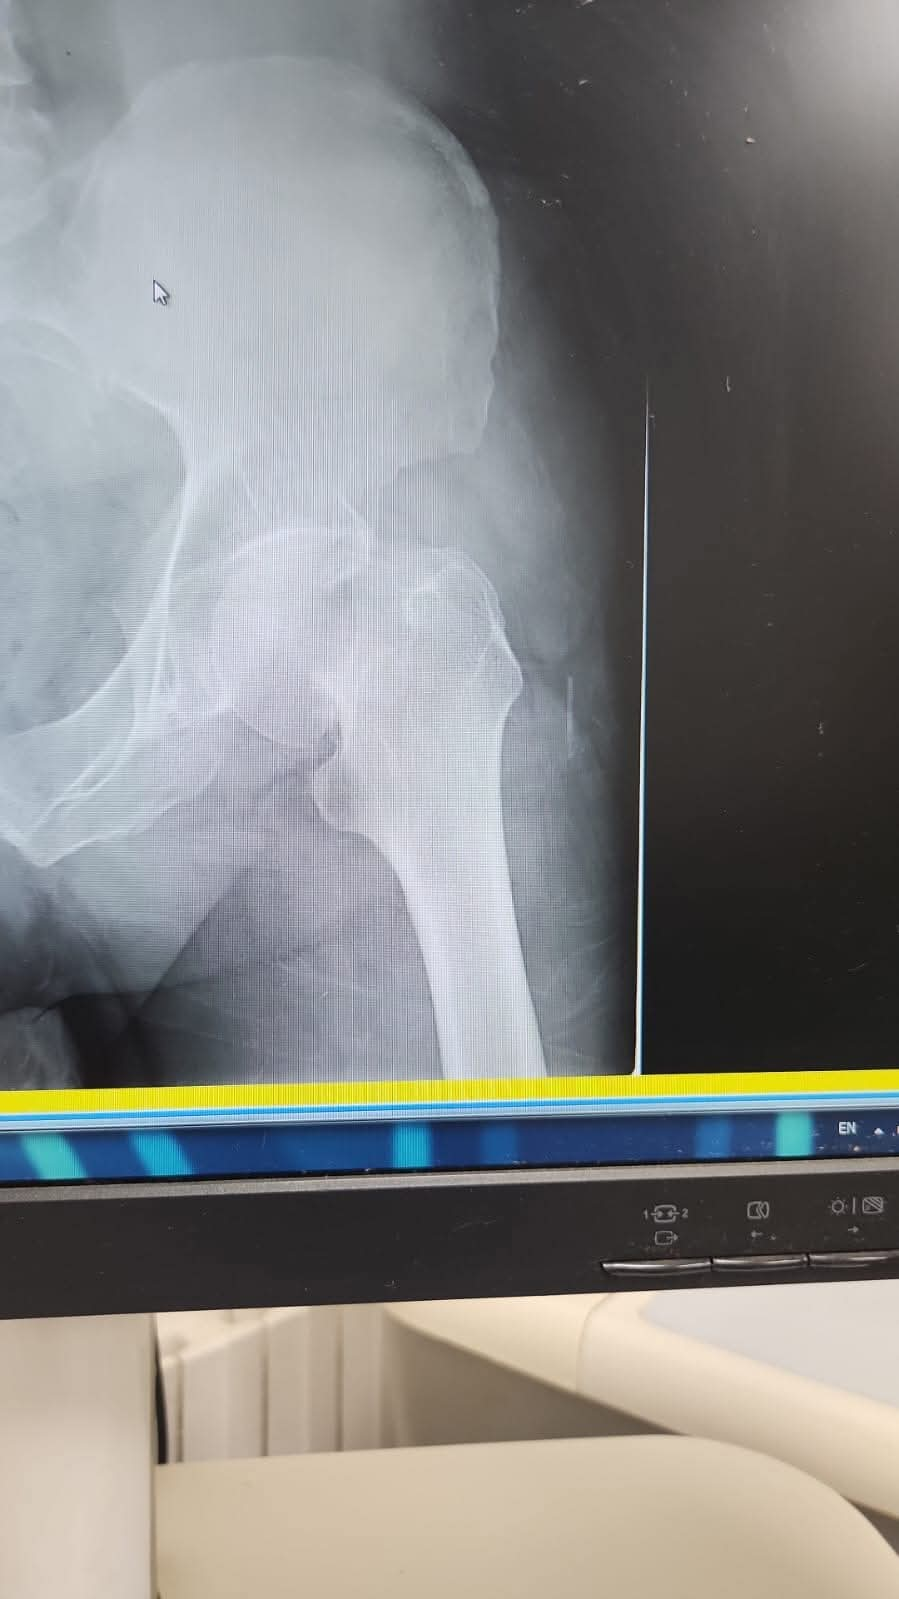

يقوم بعمليات تثبيت الكسور المعقدة بشكل طاريء وتبديل المفاصل بشكل مبرمج مما خفف على المواطنين البحث عن أسرة في مستشفيات مركزية رغم صعوبة عمليات العظام من الناحية التقنية في المستشفيات النائية إضافة الى استقبال اعداد كبيرة بالعيادات ومعالجة جميع المرضى بالطرق المثلى انه الدكتور الانسان البارع والمتميز يزيد البريزات طبيب العظام في مستشفى الاميرة سلمى / ذيبان عيادة العظام علماً بأنه كان مستشفى تحويلي منذ تاسيسه والدكتور البربزات وقبل اربع سنوات في عام 2020 منذ انتقاله للمستشفى يقوم بهذه العمليات ومن بينها عمليات نوعية لمرضى يعانون من كسور معقدة في الترقوة واجراء عمليات دقيقة ومعقدة لكسور لمرضى في مختلف أنحاء الجسم وعمليات تثبيت الكسور المعقدة وتركيب المفاصل وغيرها الكثير والديسك " وآلامه وتبعاته وعلاجه وإجراء عمليات معقده وصعبه.

وأجرى الدكتور البريزات عمليات كبرى في جراحة العظام والتي تحتاج إلى مراكز متقدمة ومتطورة. وكذلك العمل على تثبيت أغلب انواع الكسور بطريقة طارئة وتبديل المفاصل بطريقة مبرمجة بما يتناسب مع امكانات المستشفى والتي هي جزء من العمليات الدورية بمستشفى الاميرة سلمى في ذيبان والتي تخفف العبئ على المستشفيات المركزية وعلى المواطن في آن واحد.